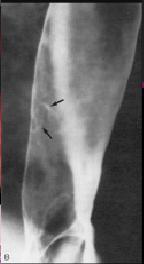

Une autre cas de

papilome oesophagien . Inmage en lacune a bord droit

de oesophage . |